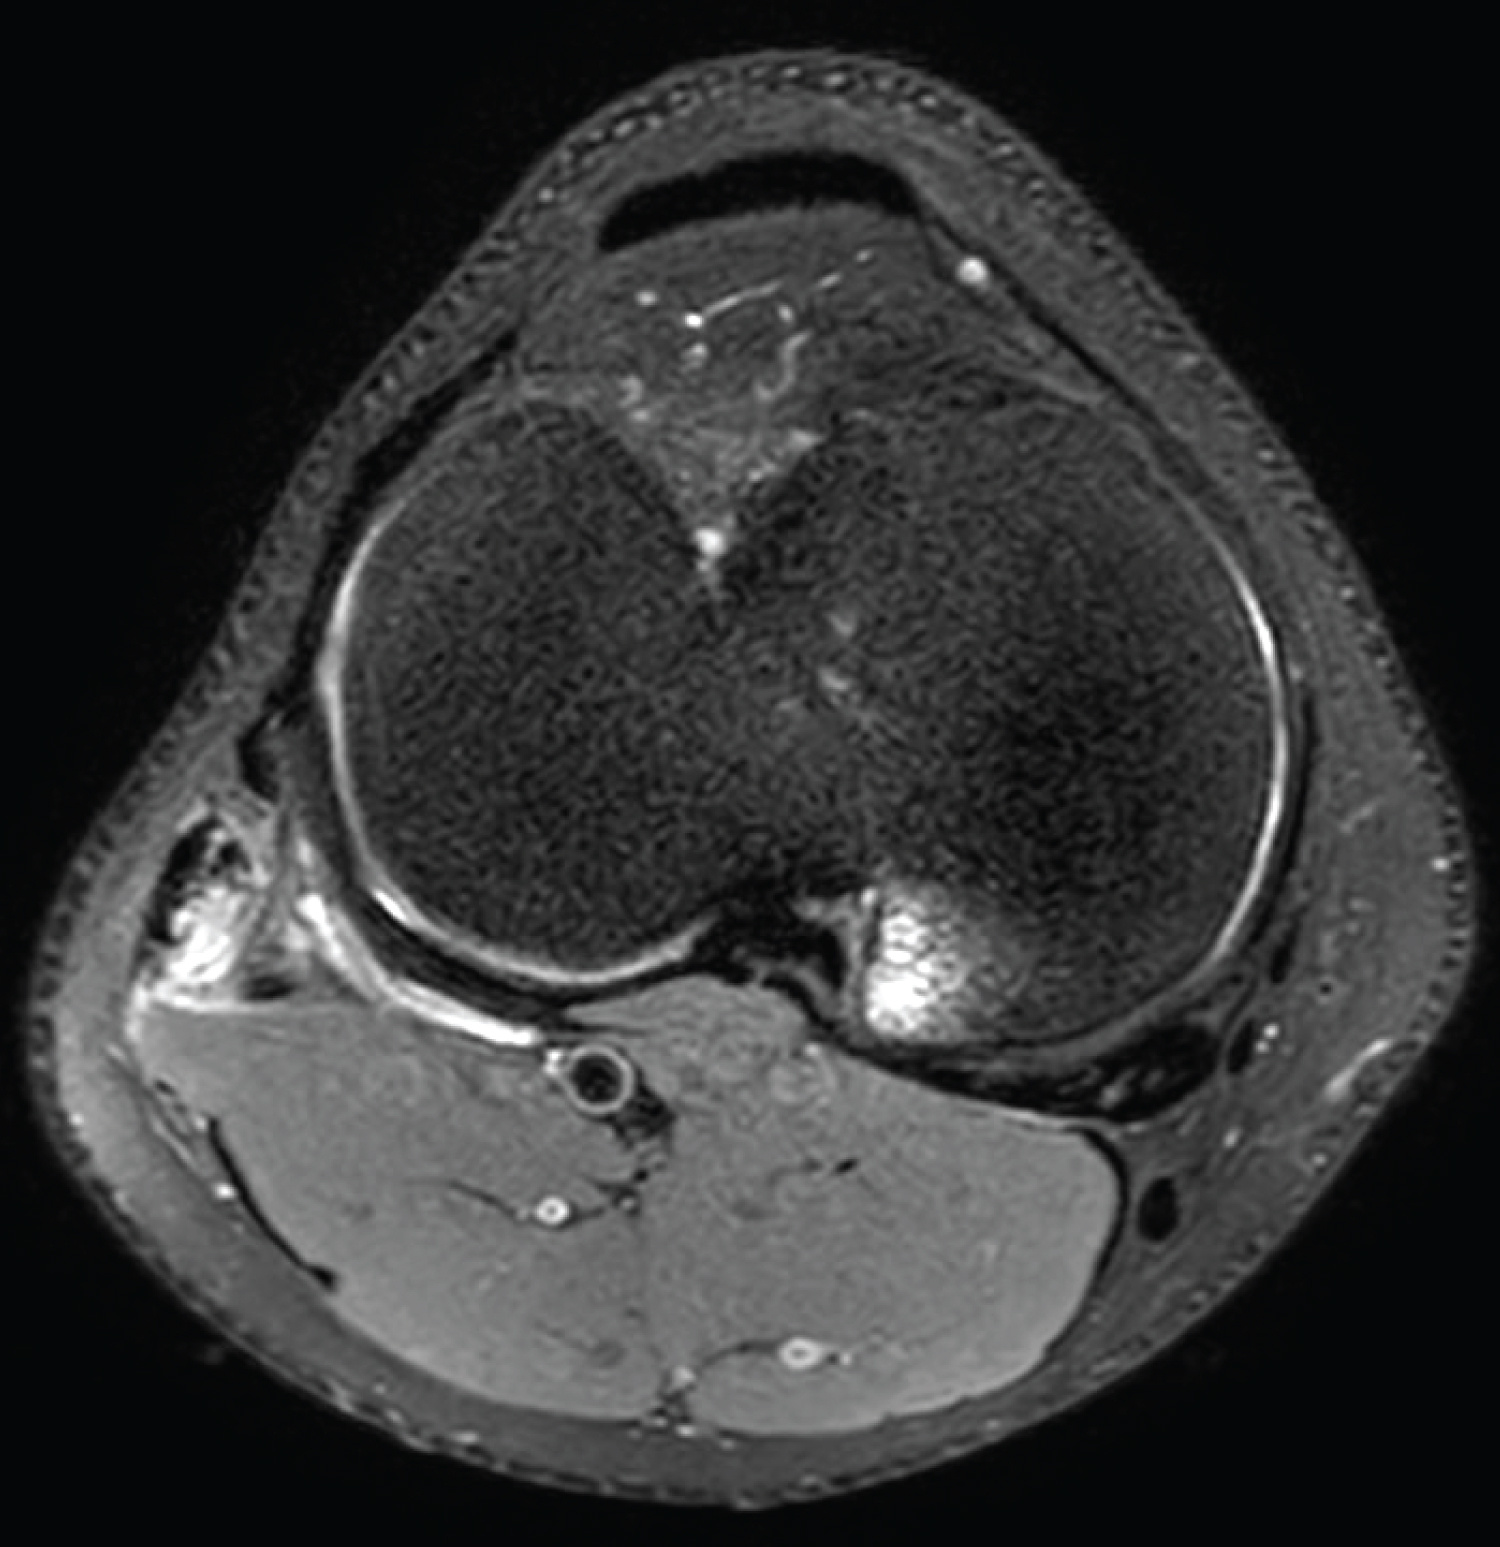

MRI also revealed marrow oedema to the posteromedial tibial plateau beneath a healthy-looking meniscus (Figure 3A). Although high signal changes were present within the posterior horn of the medial meniscus, these did not reach either articular surface to satisfy an MRI diagnosis of meniscal tear (Figure 3B). Furthermore, clinical exams tested negative for meniscal injury, and therefore this signal was felt to be in keeping with prominent vasculature, commonly seen in this young age group [12].

Figure 3: Sagittal PD-weighted SPAIR image of (A) Bone bruising around posteromedial tibial plateau area; (B) Signal changes within the posterior horn of the medial meniscus. View Figure 3

In addition, we found marginal marrow oedema to the inferomedial femoral condyle and adjacent medial menisco-capsular junction on MRI (Figure 4). We hypothesise this may have been from a direct contusion (in turn, possibly resulting in varus stress to the knee and damage to biceps femoris tendon) or possibly as part of a hyperextension and twist type mechanism of injury. As mentioned earlier, however, our subject could not explicitly recall a knee injury at any stage, rather progressively worsening knee pain and function.

Figure 4: Coronal PD-weighted SPAIR image of marginal marrow oedema to the inferomedial femoral condyle and adjacent medial meniscocapsular junction. View Figure 4

We also noted low level hyperintensity change through the Anterior Cruciate Ligament (ACL), which may reflect some local loculation of joint fluid in the notch or possibly a very low grade strain of the ACL (Figure 5).

Figure 5: Sagittal PD-weighted SPAIR image of low level hyperintensity change through the anterior cruciate ligament. View Figure 5